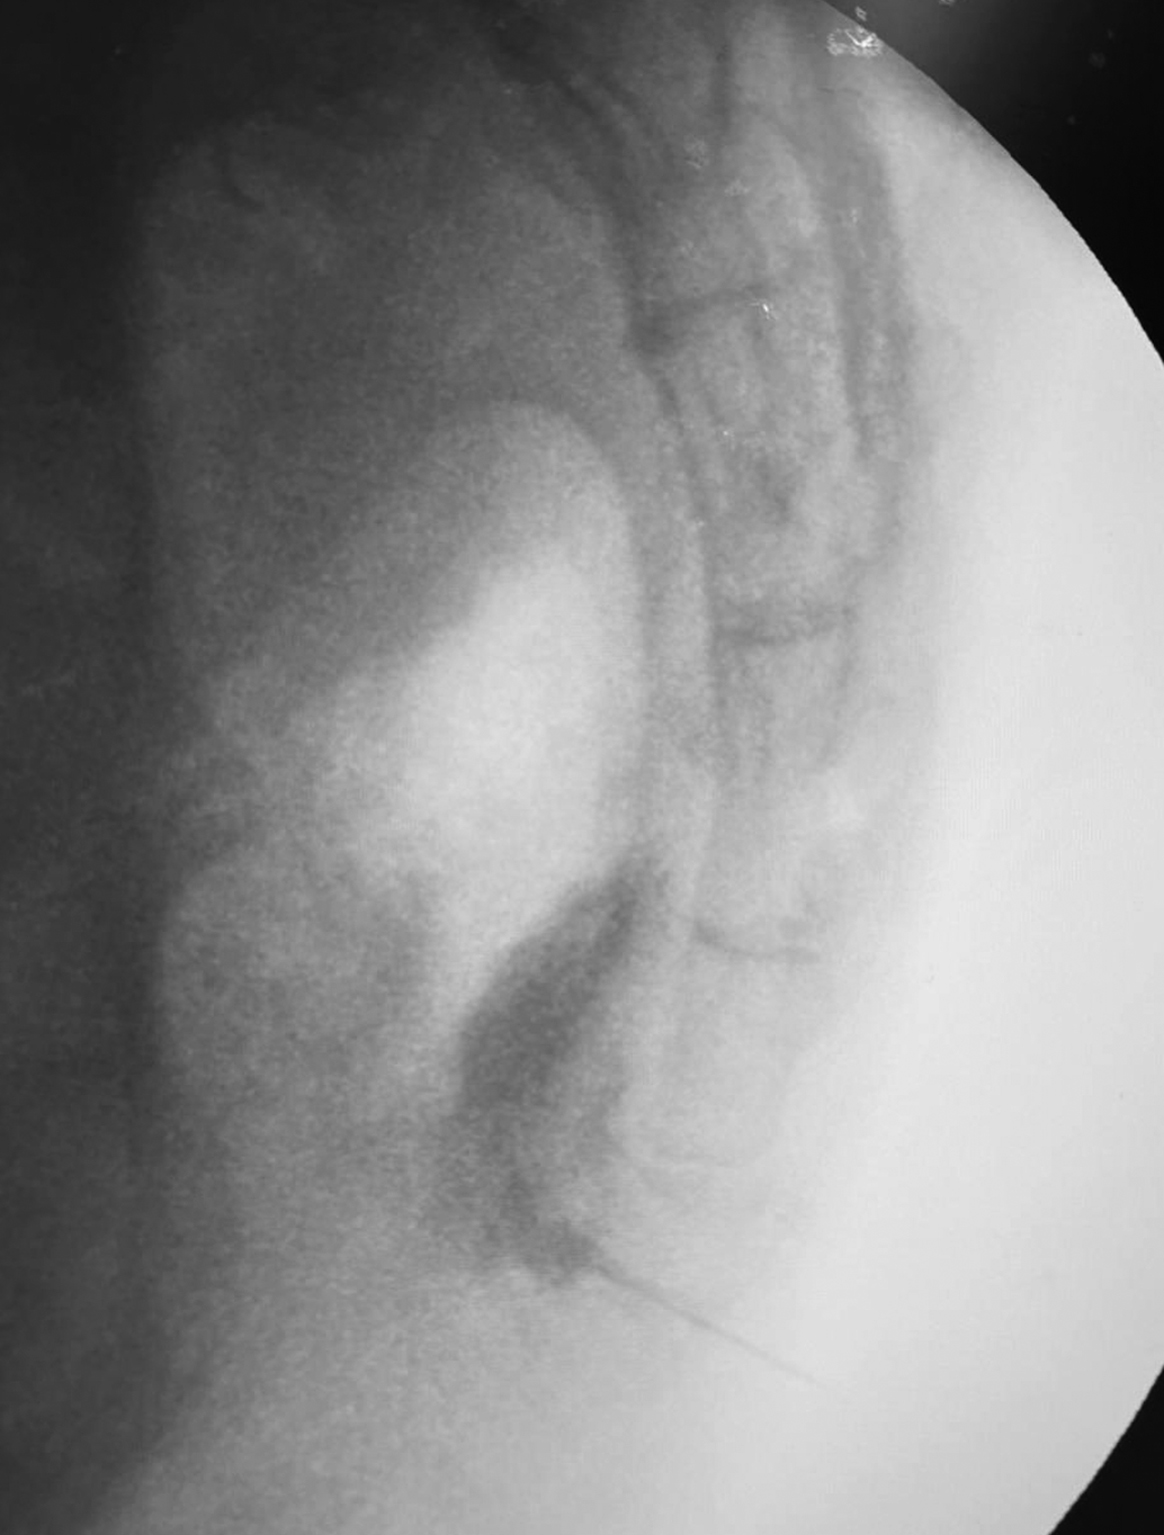

Two weeks after the surgical intervention, the patient underwent GIB using the following technique [14]. After antiseptic preparation of the skin, the target intergluteal area was covered with sterile surgical drapes. Injections were performed under fluoroscopic guidance using a C-arm. In this case, the «Cios Select with FD» device (Siemens, Germany) was used. A total of 2 mL of 2% lidocaine was administered into the subcutaneous tissue of the upper intergluteal fold as a local anesthetic, followed by the insertion of a 23G (0.6 × 30 mm) needle into the sacrococcygeal disc. The needle was advanced to the point of loss of resistance, indicating its placement anterior to the ventral sacrococcygeal ligament. Once the needle was positioned along the sacrococcygeal disc line, 1 mL of a radiopaque dye, «Tomogexol 350» (Farmak, Ukraine), diluted in saline at a 1:2–1:3 ratio, was injected. The needle position was confirmed by the appearance of a "comma" or "crescent" sign in the retroperitoneal space on lateral fluoroscopic imaging (Fig. 2). The spread of contrast within the sacrococcygeal disc indicated the need for further needle advancement. The presence of the contrast agent in the lumen of the rectum suggested posterior wall perforation and excessive needle advancement, which is an undesirable outcome. Following a negative aspiration test, confirming the absence of blood or cerebrospinal fluid, 2–3 mL of 0.5% bupivacaine and 1 mL of «Depo-Medrol®» (methylprednisolone, Pfizer, USA) were administered. One week after the GIB, the patient’s VAS score was recorded at 1 cm. The patient reported high satisfaction and was able to fully undergo the prescribed postoperative rehabilitation course.

Fig. 2. GIB under X-ray control using a trans-sacrococcygeal approach, lateral projection. The needle is visualized passing through the sacrococcygeal disc, with contrast staining of the ganglion impar